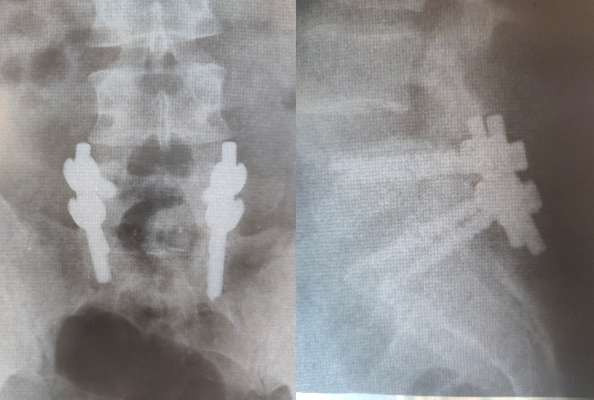

Kažkuriuo metu gyvenimas mane nubloškė į Airiją, kur teko dirbti mėsos fabrike ir tada bam ……gyvenimas apsisuko 180° kampu . Darbe patiriu stuburo traumą, po jos sekė keli metai gydymo , gyvenimas nuolatiniame skausme , po to – 2010 m viena stuburo operacija , 2011- antroji stuburo operacija, stuburo L5-S1 dalies fiksacija, keturi metaliniai varžtai ir verdiktas: „Sportas tavo gyvenime sušluotas po kilimu“ ( kaip atrodo mano stuburas po operacijų- galite pamatyti prie šio įrašo esančioje galerijoje). Aš tada tuo patikėjau. Gydytojas sakė jog aplamai turėčiau džiaugtis jog vaikštau į ne sėdžiu beįgaliojo vežimėlyje …..